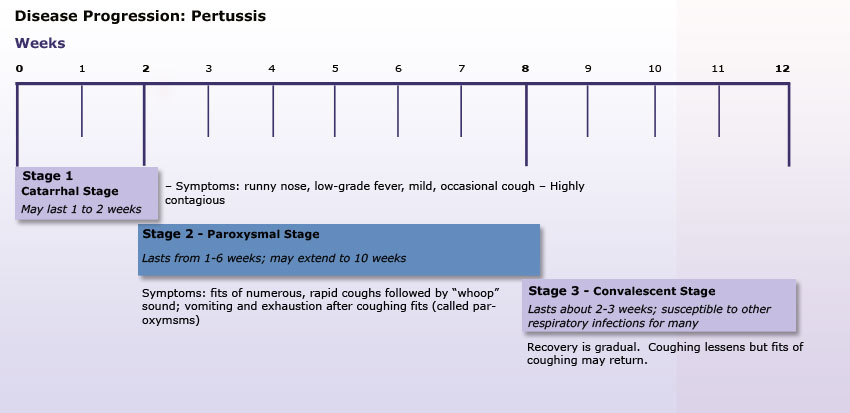

Pertussis:

“Whooping Cough”, Bordetella Pertussis bacteria, from respiratory droplets

“Whooping Cough”, Bordetella Pertussis bacteria, from respiratory droplets- Symptoms: cold symptoms for 1-2 weeks, followed by overwhelming cough, sometimes vomiting, causing death in infants from suffocation, apnea

- Complications: pneumonia, convulsions, encephalopathy (infection of the brain)

- Death/Statistics: death rates of 1.6% in America, 4% globally. 48.5 million cases annually worldwide, and 295,000 deaths.

- This is not a disease from a foreign country. This disease is here, in Massachusetts, in the Pioneer Valley.Read the sad tale of Brady Alcaide from Chicopee, who died at 6 weeks of age in 2012. Too young to get the vaccine.

- Brady’s Story

- Pertussis is a bacteria that you can treat with antibiotics if you catch it early enough. After the first 2 weeks of the “cold symptoms”, however, any antibiotic treatment only prevents its spread, it does not stop the deadly “whoop” cough. This cough can last for months.